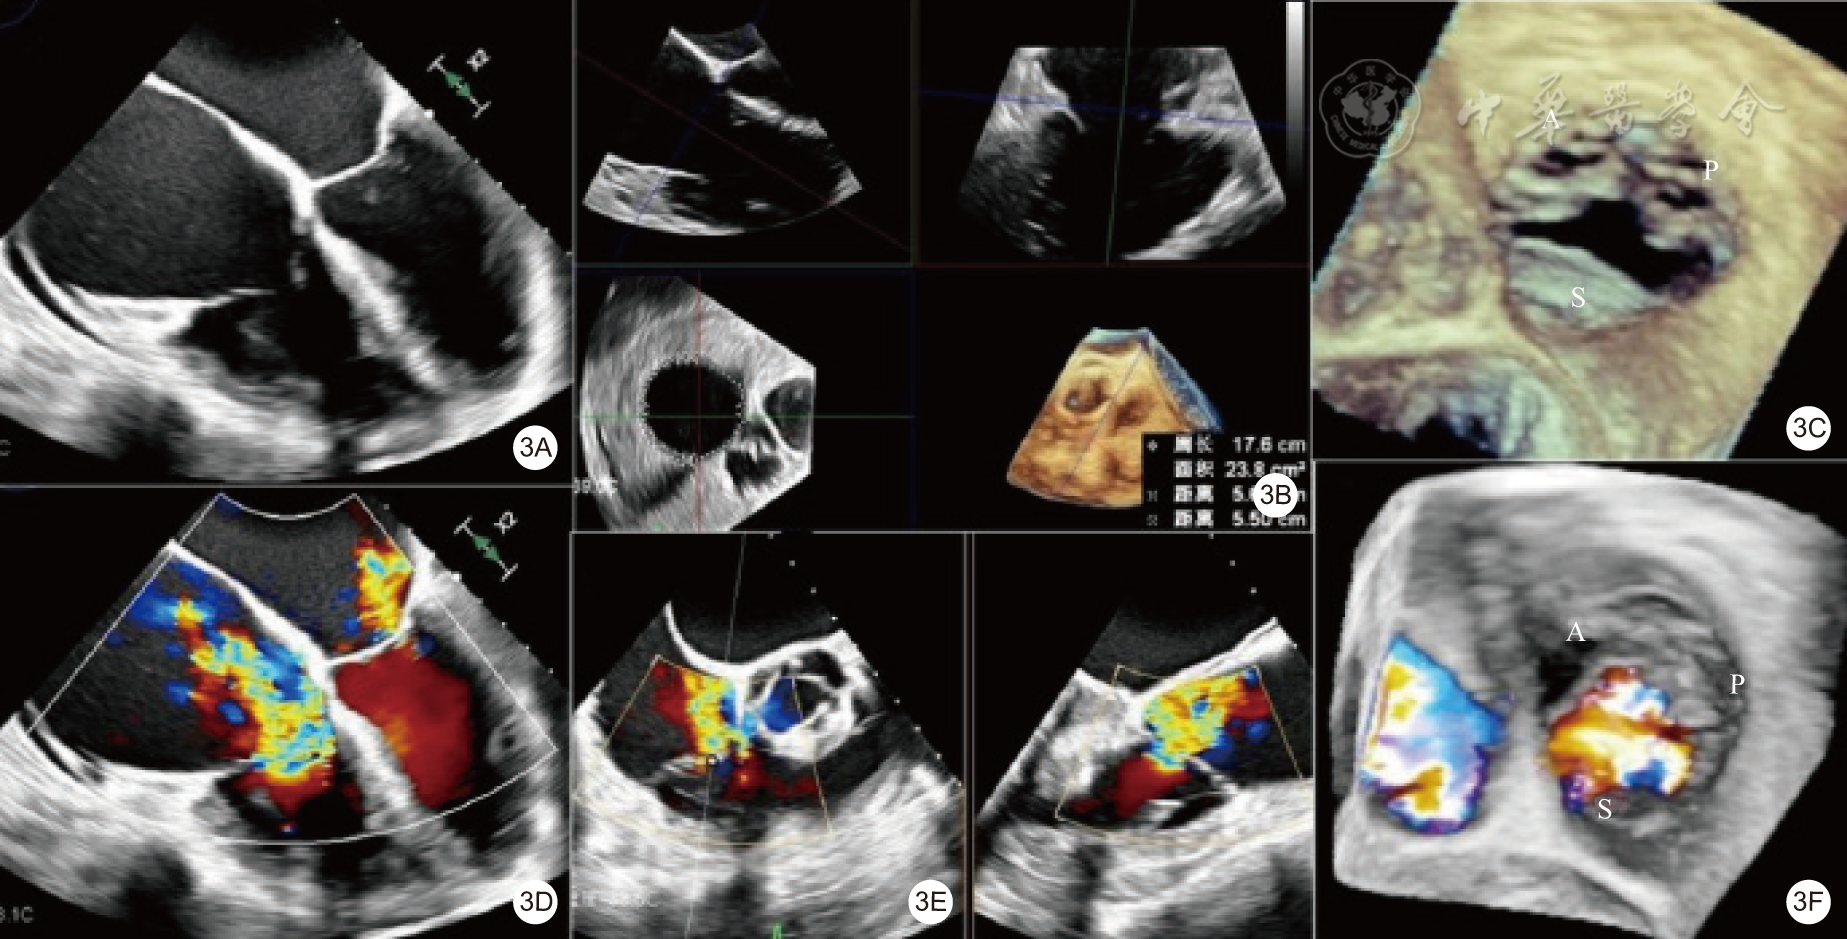

图2 术前 TTE 评估(2A为心尖四腔心切面,显示左、右心房明显增大及右心室轻度增大,房性功能性 TR,对合高度降低,三尖瓣关闭见缝隙;2B为胸骨旁右心流入道切面,显示右房室增大,室性功能性 TR,瓣叶栓系,三尖瓣关闭见较大缝隙;2C为心尖四腔心切面,彩色多普勒显示重度 TR;2D为胸骨旁右心流入道切面,彩色多普勒显示重度 TR;2E为剑突下三尖瓣短轴切面显示三尖瓣为正常的三叶瓣;2F为剑突下三尖瓣短轴切面显示三尖瓣为异常的四叶瓣,其中后叶分为二叶;2G为根据 PISA 法估测EROA 及 RVol)注:TTE为经胸超声心动图,TR为三尖瓣反流,PISA为近端等速表面积,EROA为有效反流口面积,RVol为反流容积